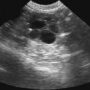

При выявлении бактериурии у беременных, необходимо назначить тщательное обследование женщины, включающее лабораторные анализы и УЗИ почек. Так как на фоне бактериурии достаточно часто возникает пиелонефрит, то беременным, обычно, назначают курс профилактического лечения.